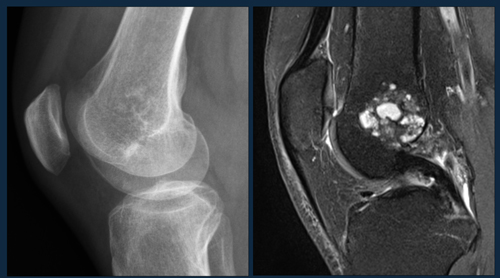

Cartilage tumors